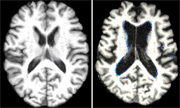

(左)ビタミンB12が多い人の脳スキャン

(右)ビタミンB12が少ない人の脳スキャン

肉や魚,牛乳などに含まれるビタミンB12には,老化による脳の萎縮を防ぐ効果があるかもしれない。こんな研究結果が明らかになった。61~87歳の100人以上を対象に,血液中にあるビタミンB12の量を測定し,脳スキャンと記憶テストを実施したところ,ビタミンB12が多かった人は少なかった人に比べて6倍も脳が萎縮しにくかった。この結果によると,食事でビタミンB12を多く摂ることにより,老化による記憶力の減退を防ぐことができる可能性がある。ただし,ビタミン剤に同様の効果があるかは明らかではない。(吉田素子)

For the study, 107 people between the ages of 61 and 87 underwent(5) brain scans(6), memory testing(7) and physical exams(8). The researchers from the Oxford Project to Investigate Memory(9) and Ageing(10) (OPTIMA) also collected blood samples to check vitamin B12 levels. Brain scans and memory tests were also performed again five years later.

The study, published in the journal Neurology(11), found that people who had higher vitamin B12 levels were six times less likely to experience brain shrinkage(12) compared with those who had lower levels of the vitamin in their blood. None of the people in the study had vitamin B12 deficiency(13).